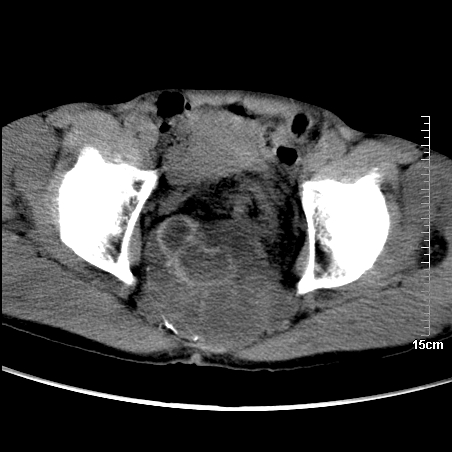

标题: CT16886:骶尾部占位:1.脊索瘤?2.巨细胞瘤?

增强:

1、骶尾部巨大软组织肿块,部分骶尾骨以被软组织肿块代替,呈不规则侵蚀;病变突向盆腔内;增强扫描病变呈不均质强化;首先考虑脊索瘤。不支持的一点就是病变内无钙化。

2、发生于骶尾椎者须与骨巨细胞瘤鉴别,骨巨细胞瘤一般发在上疗骶椎,肿瘤内无钙化,一般无侵袭性生长的表现。